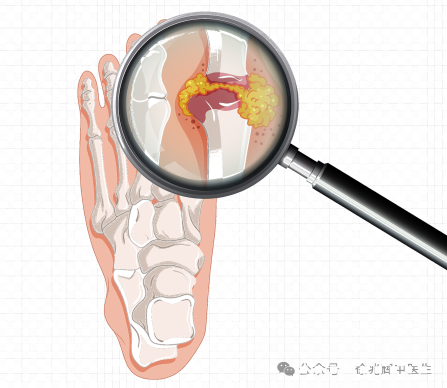

一、痛风性关节炎:藏在关节里的“隐形杀手”

痛风性关节炎是一种因尿酸盐结晶沉积关节引发的关节剧烈疼痛,患者常经历夜间因突发的关节剧烈疼痛、红肿而惊醒,常常描述为“痛如虎噬骨”。据统计,我国高尿酸血症患者已超1.8亿,其中约10%会发展为痛风。然而,痛风的诊断并非易事——假性痛风、类风湿性关节炎、化脓性关节炎甚至某些外伤都可能伪装成它的症状,导致误诊率高达30%。如何揪出“真凶”?双源CT技术的出现,让真相无所遁形。

双源CT通过两组不同能量的X射线同步扫描,利用物质对高低能射线的吸收差异,精准识别组织成分。其核心技术在于:

1. 双能量减影:自动分离尿酸结晶(呈现亮绿色)与钙化灶(显示为紫色);

2. 亚毫米级分辨率:可检测直径0.5mm的微小结晶,比传统CT敏感度提升40%;

3. 三维成像技术:立体展示结晶在滑膜、软骨甚至肌腱中的分布。